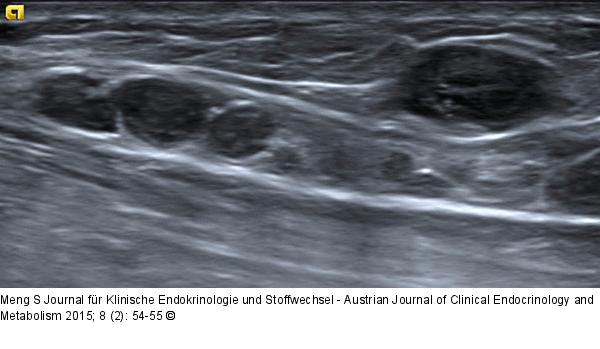

Abbildung 10: Ultraschall-Lymphknoten Muster der Lymphadenopathie. Fallen mehrere alterierte Lymphknoten auf, kann das Befallmuster v. a. im Hinblick auf die Anamnese aussagekräftig sein. Lymphknotenmetastasen nach lokoregionärem Melanom. |

Muster der Lymphadenopathie. Fallen mehrere alterierte Lymphknoten auf, kann das Befallmuster v. a. im Hinblick auf die Anamnese aussagekräftig sein. Lymphknotenmetastasen nach lokoregionärem Melanom. |